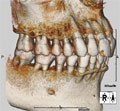

当院では、精密検査機器として歯科専用のCTスキャナーを使用しています。 |

| あごの中に埋まっている歯を立体的に診断することができます。 |

三次元の立体画像であらゆる方向から観察できます。

また自由に断面図を作成して診断することができます。 |

| インプラント治療において、あごの骨に埋めるインプラントを立体的にとらえて治療計画を立てられます。 |

インプラントの数、長さ、太さをあらゆる方向から診断して正確に決定することができます。

神経などを避けて安全な位置、方向、埋める深さを決められます。